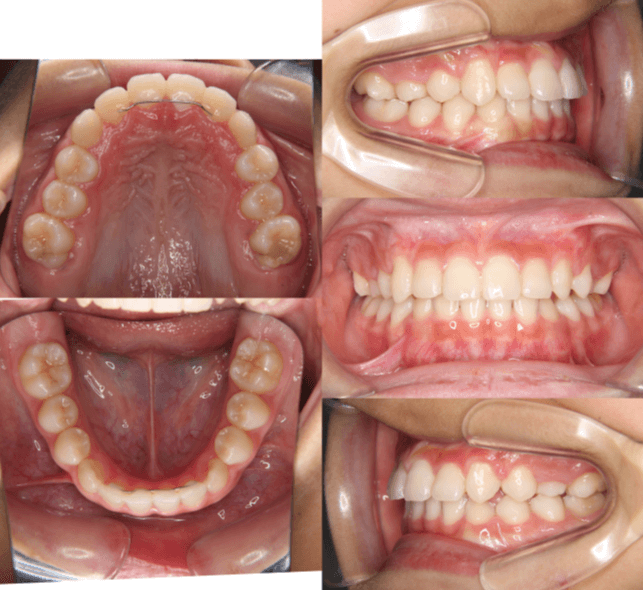

| 年齢・性別 | 7歳1ヶ月の男児 |

|---|---|

| 主訴 | 歯の生えるスペース不足が懸念され、歯列の乱れ(叢生)を整えるために来院された患者様です。 |

| 治療期間・回数 | 1年3ヶ月・11回 |

| 費用 | 420,000円(税別) |